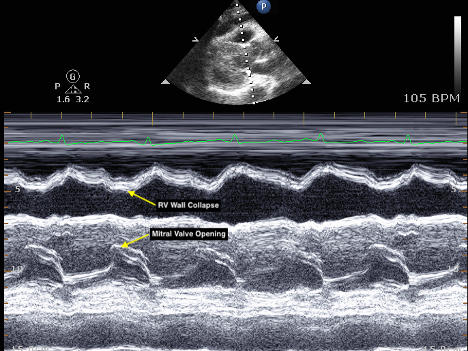

Cardiac tamponade

What condition is seen in the following m-mode image?